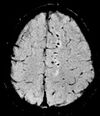

T2* Postexcitation refocused GRE with small flip angle.[19] Low signal from hemosiderin deposits (pictured) and hemorrhages.[19] Effective T2-weighted MRI of hemosiderin deposits after subarachnoid hemorrhage.png